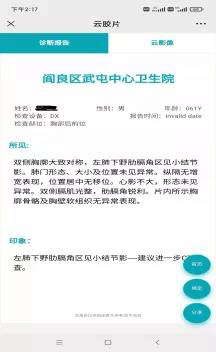

“云”影像,简单地说就是抛弃传统胶片,通过手机、ipad等智能终端查看检查报告和片子。只需微信扫一扫报告单上的二维码,随时随地查阅影像和电子报告,方便携带和保存。如有会诊需求,也可以把二维码拍照发给相关医师,医师只需识别二维码就可以查看病人的检查结果。

图2 手机上查看检查报告